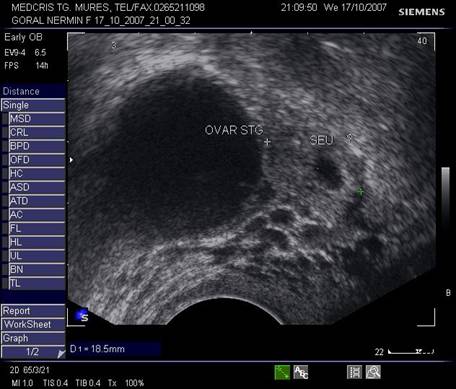

Fig nr 55 Langa ovarul stang, o formatiune ovalara ( intre calipere ) de 18 mm, cu ecou hipoecogenic central, la 6 sapt.de amnoree

![]()